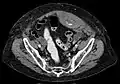

Rectus sheath hematoma

A rectus sheath hematoma is an accumulation of blood in the sheath of the rectus abdominis muscle. It causes abdominal pain with or without a mass.